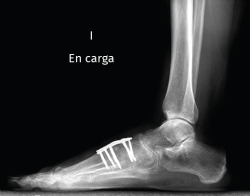

El estudio radiológico en carga permite identificar un patrón variable de artrosis cuneometatarsiana, donde se pueden identificar secuelas de fracturas antiguas.

Figura 1. Artrosis primaria de la primera articulación cuneometatarsiana.

Existen distintas opciones de osteosíntesis con tornillos y/o placas. Actualmente, disponemos de diferentes diseños de placas: placas de tipo “Pi” que fijan CMM1-CMM2, placas plantares, mediales, medioplantares o dorsales. Recomendamos el empleo de placas “Pi” si es preciso artrodesar CM-M2 y el uso de placas medioplantares o plantares para la artrodesis aislada de CM-M1, que desde el punto de vista biomecánico son más apropiadas (Figuras 1 a 3). Otro tema de debate es el empleo de injerto óseo esponjoso autólogo o de sustitutivos óseos como la matriz ósea desmineralizada o trifosfatos cálcicos. Recomendamos, especialmente en pacientes menores de 50 años, el empleo de injerto autólogo de cresta ilíaca.